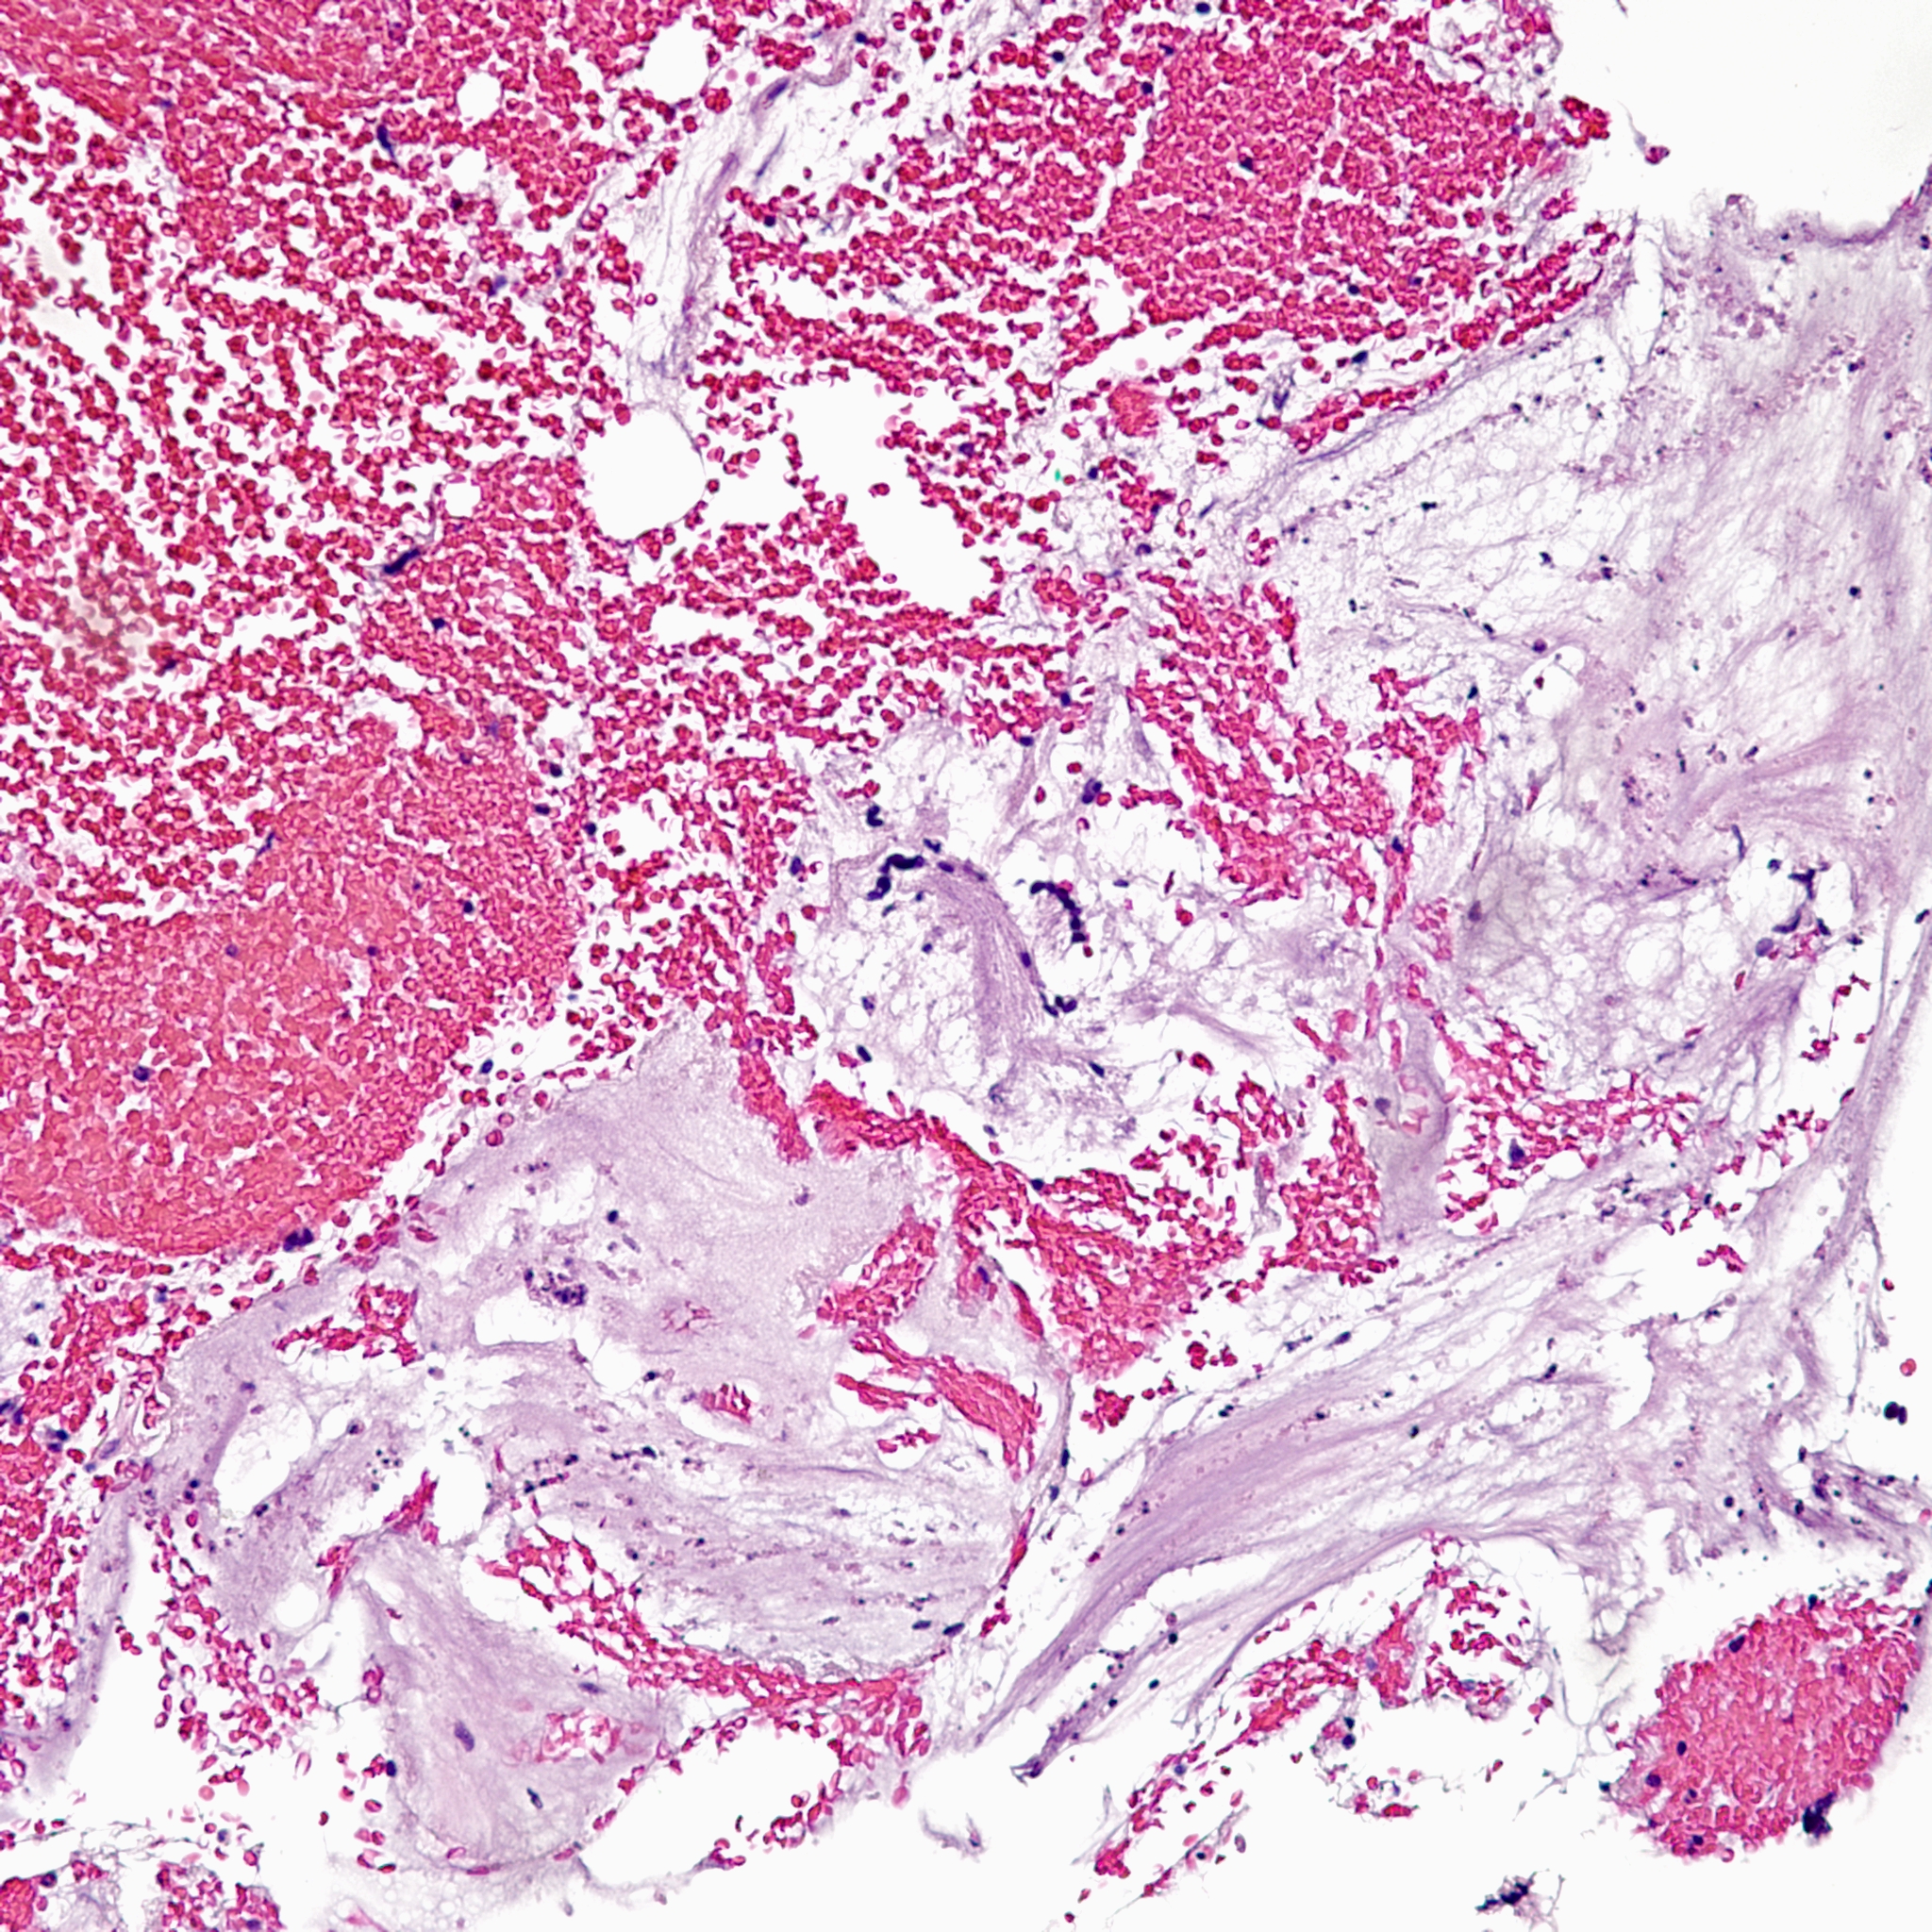

On higher power, we can see that this nodule is mostly composed of this pink amorphous material with interspersed large, round cells with abundant eosinophilic and sometimes clear cytoplasm (arrows). There are essentially no mitoses and atypia is not very prominent.

On higher power of the acellular areas we can see vague outlines of the cells that may have been there and have now degenerated into this hyalinized stroma (black arrows). The cells that remain are large, round to oval, with dense eosinophilic to clear cytoplasm (red arrows).